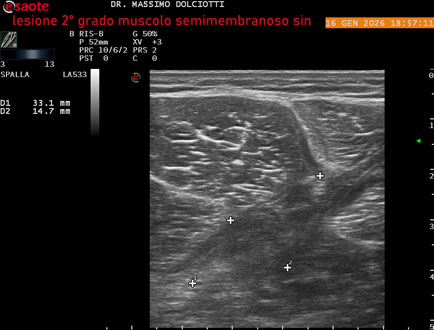

Ecografia del: 16/01/2025

Età Paziente: M 23 anni

Motivazione dell'esame: dolore coscia sinistra da tre giornii.

Commento all'esame: le immagini ed il video documentano il muscolo semimembranoso sinistro disomogeneo per area iso-ipoecogena delle dimensioni di 38 x 14,7 mm per asse corto trasversale, 81 x 22 mm per asse longitudinale, come da lesione di 2° grado, con minimo versamento siero-ematico intramuscolare.

Conclusioni: lesione di 2° grado del muscolo semimembranoso sinistro (2nd degree lesion of the left semimembranosus muscle).